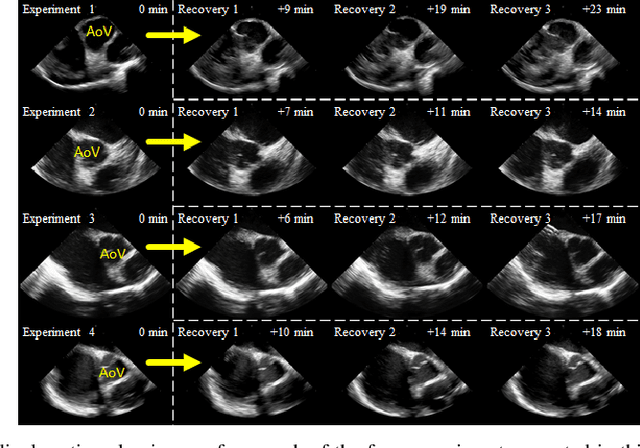

Abstract:Purpose: Intra-Cardiac Echocardiography (ICE) is a powerful imaging modality for guiding cardiac electrophysiology and structural heart interventions. ICE provides real-time observation of anatomy and devices, while enabling direct monitoring of potential complications. In single operator settings, the physician needs to switch back-and-forth between the ICE catheter and therapy device, making continuous ICE support impossible. Two operators setup are therefore sometimes implemented, with the challenge of increase room occupation and cost. Two operator setups are sometimes implemented, but increase procedural costs and room occupation. Methods: ICE catheter robotic control system is developed with automated catheter tip repositioning (i.e. view recovery) method, which can reproduce important views previously navigated to and saved by the user. The performance of the proposed method is demonstrated and evaluated in a combination of heart phantom and animal experiments. Results: Automated ICE view recovery achieved catheter tip position accuracy of 2.09 +/-0.90 mm and catheter image orientation accuracy of 3.93 +/- 2.07 degree in animal studies, and 0.67 +/- 0.79 mm and 0.37 +/- 0.19 degree in heart phantom studies, respectively. Our proposed method is also successfully used during transeptal puncture in animals without complications, showing the possibility for fluoro-less transeptal puncture with ICE catheter robot. Conclusion: Robotic ICE imaging has the potential to provide precise and reproducible anatomical views, which can reduce overall execution time, labor burden of procedures, and x-ray usage for a range of cardiac procedures. Keywords: Automated View Recovery, Path Planning, Intra-cardiac echocardiography (ICE), Catheter, Tendon-driven manipulator, Cardiac Imaging

Abstract:Intra-cardiac Echocardiography (ICE) has been evolving as a real-time imaging modality of choice for guiding electrophiosology and structural heart interventions. ICE provides real-time imaging of anatomy, catheters, and complications such as pericardial effusion or thrombus formation. However, there now exists a high cognitive demand on physicians with the increased reliance on intraprocedural imaging. In response, we present a robotic manipulator for AcuNav ICE catheters to alleviate the physician's burden and support applied methods for more automated. Herein, we introduce two methods towards these goals: (1) a data-driven method to compensate kinematic model errors due to non-linear elasticity in catheter bending, providing more precise robotic control and (2) an automated image recovery process that allows physicians to bookmark images during intervention and automatically return with the push of a button. To validate our error compensation method, we demonstrate a complex rotation of the ultrasound imaging plane evaluated on benchtop. Automated view recovery is validated by repeated imaging of landmarks on benchtop and in vivo experiments with position- and image-based analysis. Results support that a robotic-assist system for more autonomous ICE can provide a safe and efficient tool, potentially reducing the execution time and allowing more complex procedures to become common place.